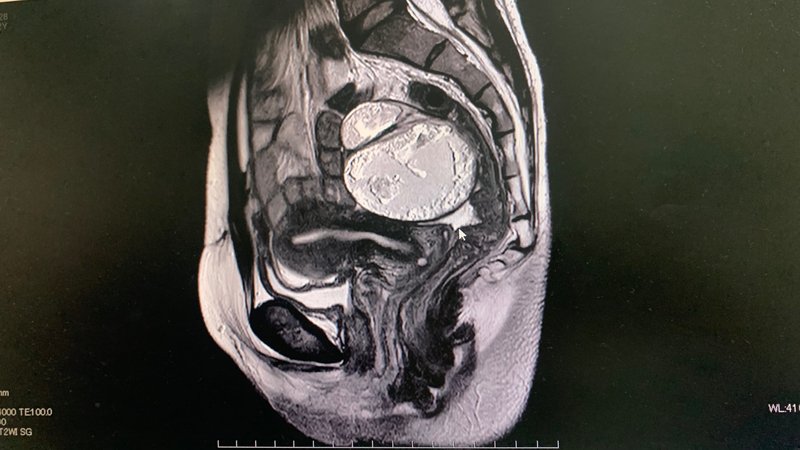

卵巣嚢腫により腰痛を経験する人もいます。 2019年の分析では、腰痛を持つ400人のMRI画像が研究されました。脊椎に関係のない痛みを感じた患者90人のうち、40人(44.5%)に卵巣所見があった。

卵巣嚢腫が大きくなると、腰痛を引き起こす可能性が高くなります。これが起こると、腹部の臓器や組織が圧迫され始め、背中に痛みや不快感が生じることがあります。

大きな嚢胞はまれです。ほとんどの卵巣嚢腫は数回の月経周期後に消えますが、 1~3センチくらい直径 – 約 1 インチ以下。非常にまれなケースですが、嚢胞は直径 15 ~ 30 センチメートル (約 6 ~ 12 インチ) まで成長することがあります。